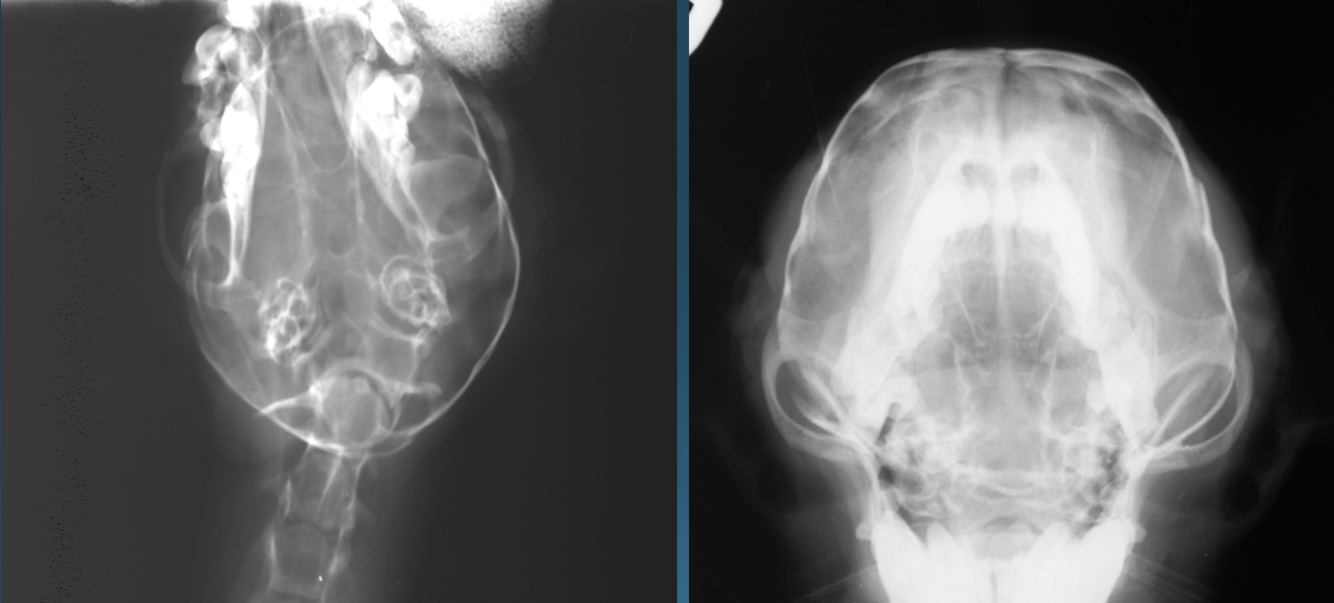

What is shown in these images?

Top Left and Right:

-hydrocephalus with doming of cranial vault

Bottom Left:

-normal

thinning of calvarium due to hydrocephalus